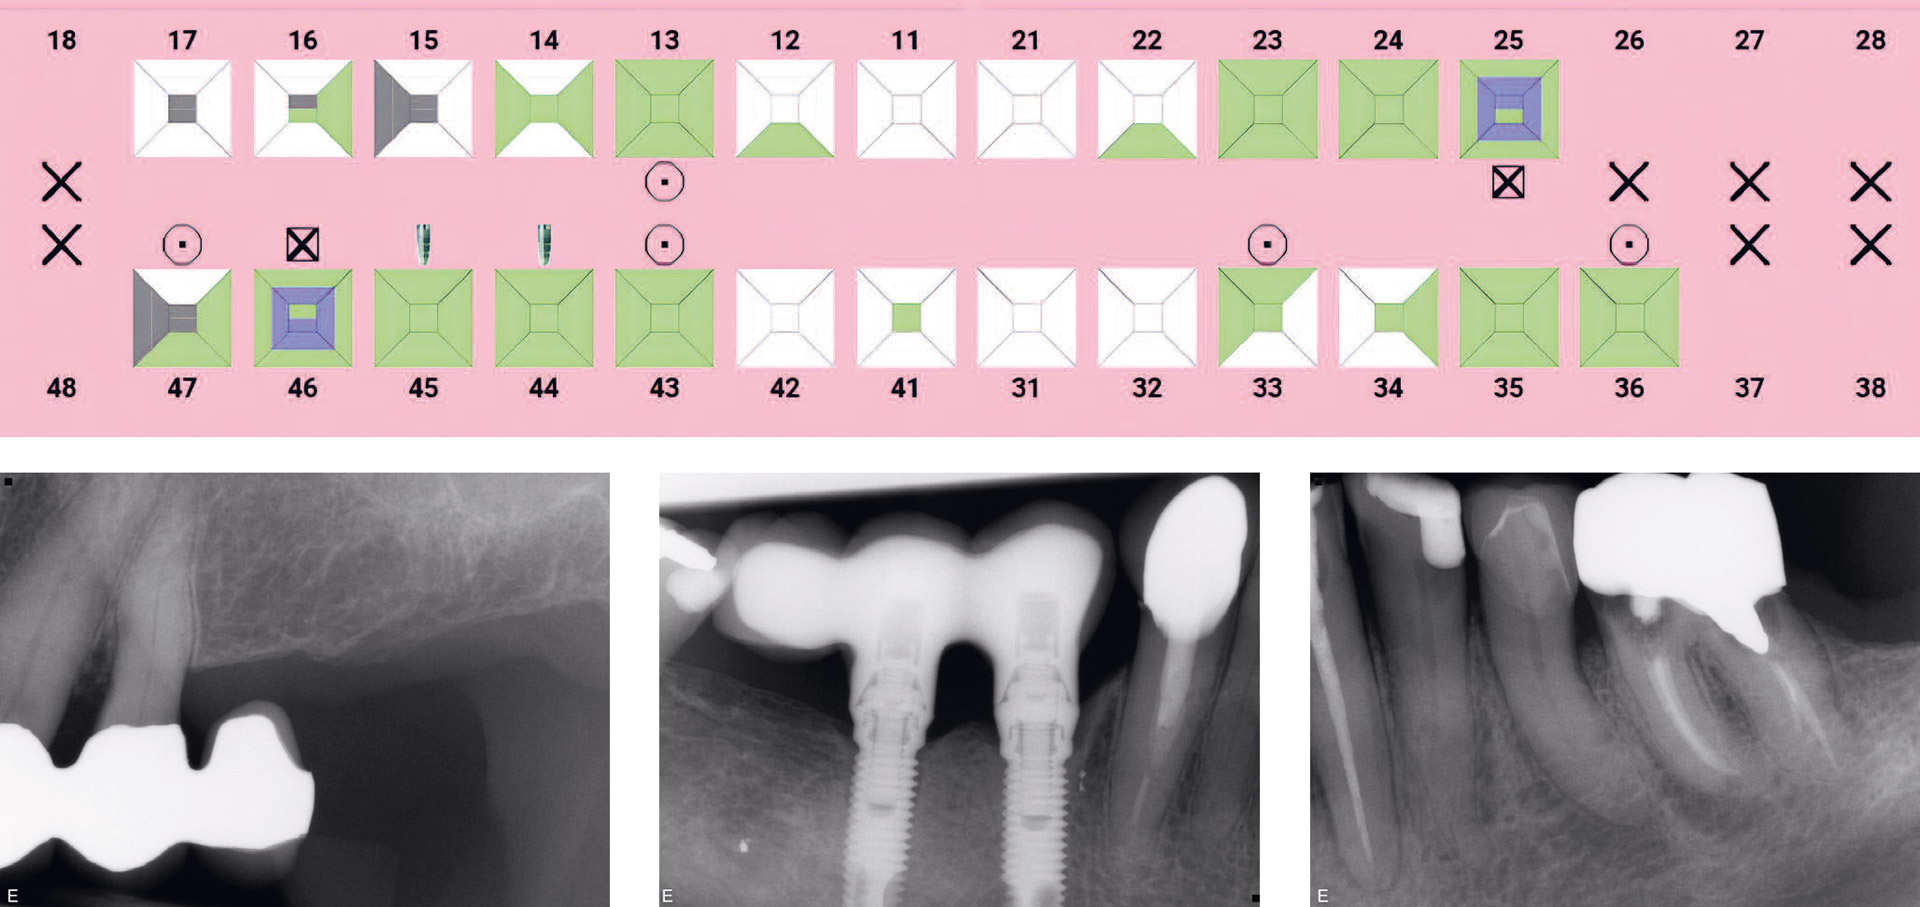

Today, most dental records are electronic, but historic handwritten or typed AM record material is equally important for identification. The FO must interpret and import all AM dental information into a special identification record system (figure 4).

Figur 4

Figure 4. AM dental status (4a) and a few selected aspects of intraoral radiographs (4b, 4c, 4d and 4e) from the AM dental record of the person suspected to be the deceased in PM case shown in figure 3.